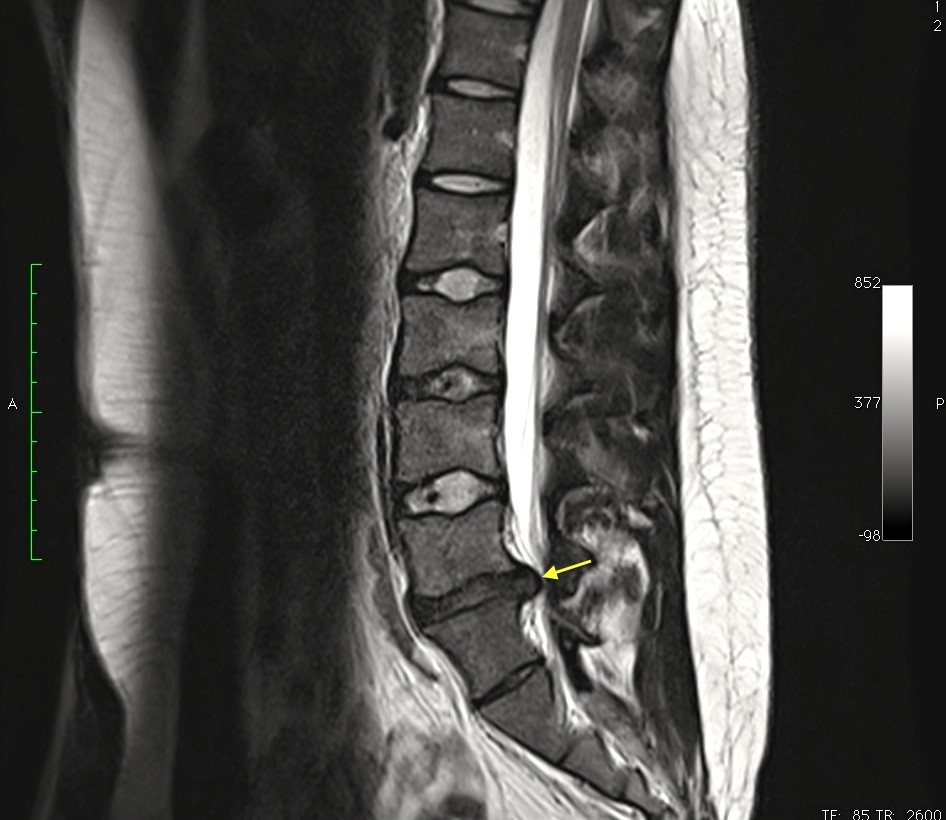

Therefore, we call disc herniation the degeneration, displacement and exit of the vertebral disc, almost always with injury and rupture of its structure, out of its place, usually giving rise to an affectation of neighboring structures.

It is accompanied by inflammation and pain of the structures of the vertebral canal: the spinal cord, the meninges, the cauda equina in the lumbar levels or also, the roots and dorsal ganglia that come out of the spine through the holes of conjunction.

Finding a herniated disc in an imaging test does not necessarily imply pathology, but having low back pain and finding an image of a herniated disc almost always points to it as the cause of it.

Complementary imaging tests, such as magnetic resonance imaging, are excellent tools that allow us to specify the origin of a problem but, as we like to repeat, «we do not treat complementary tests, we do not treat MRIs, we treat patients», that is, It is the symptoms, the patient’s complaint that makes us seek treatment.